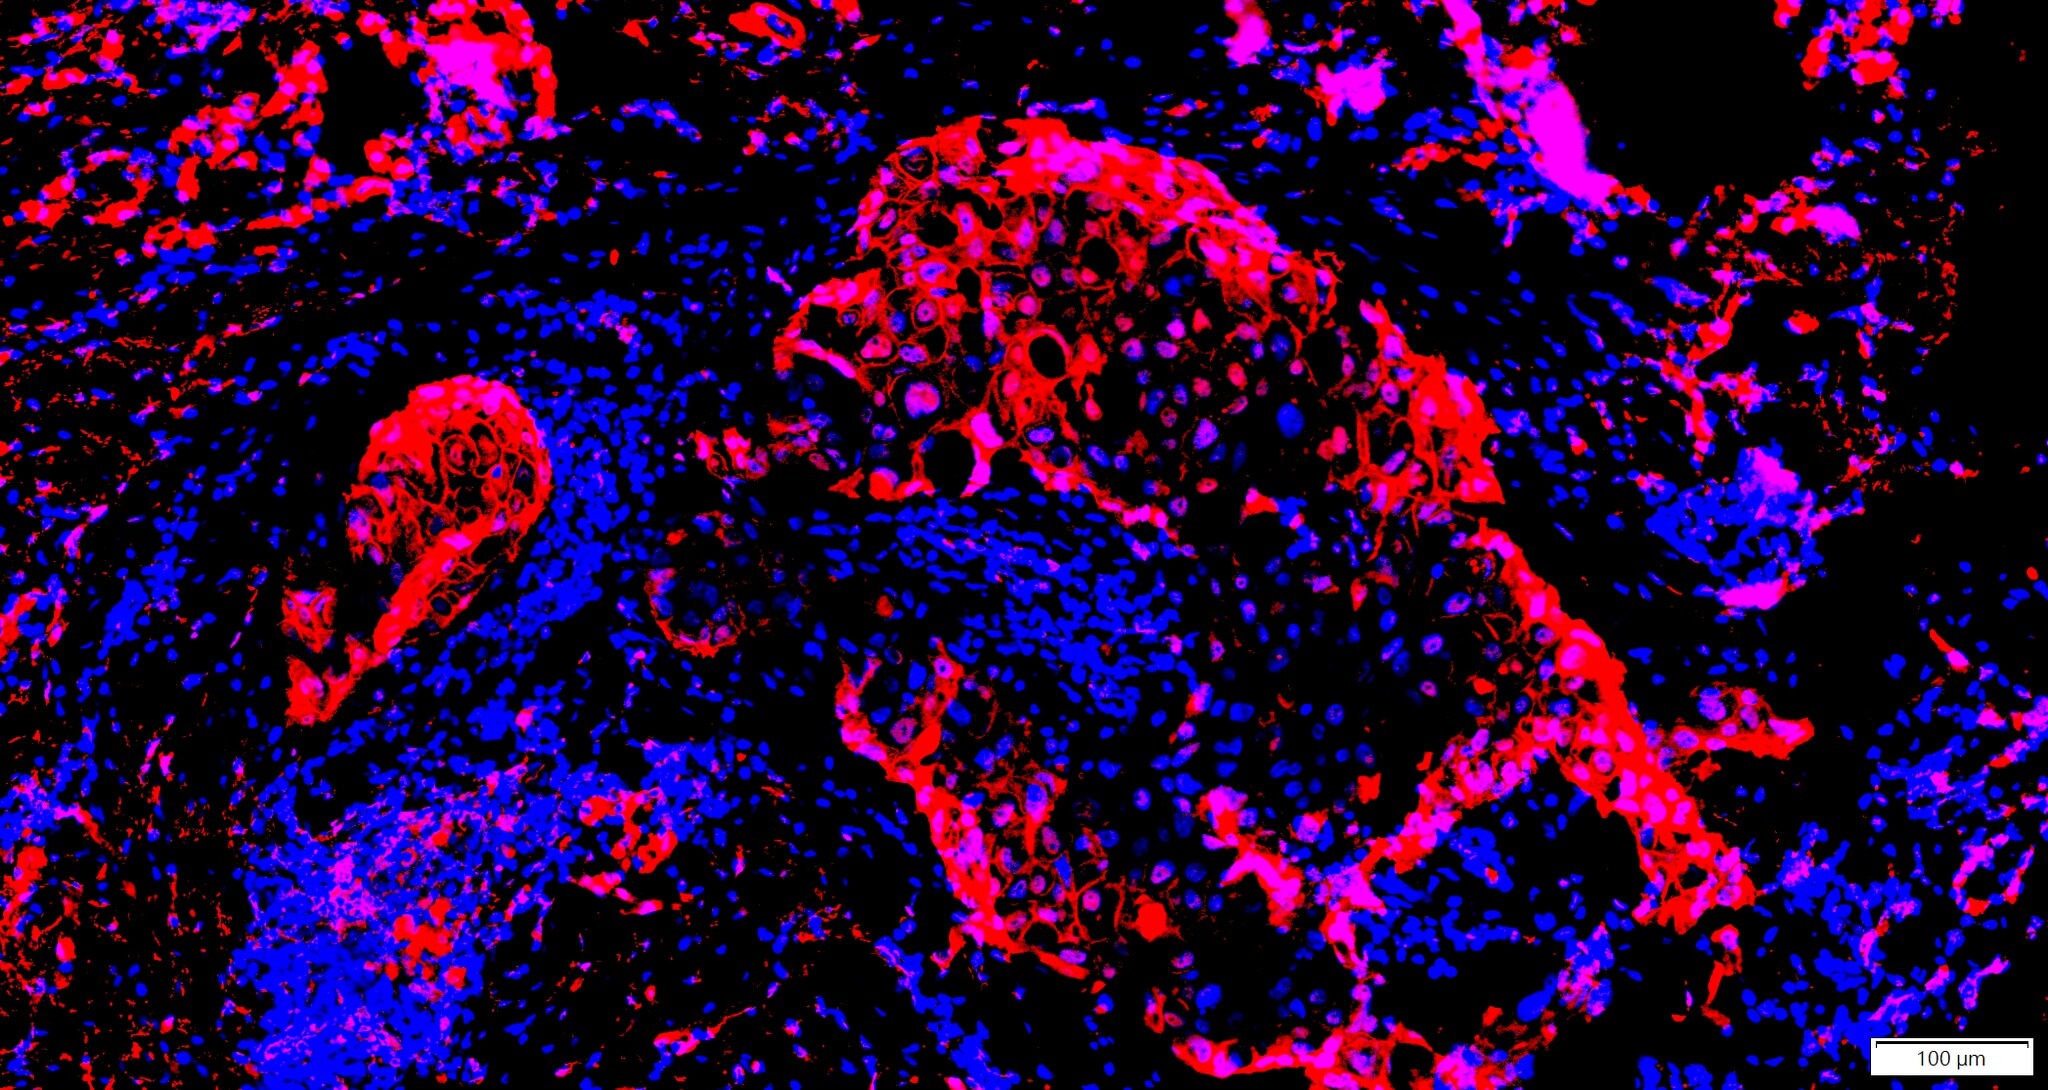

IF螢光染色